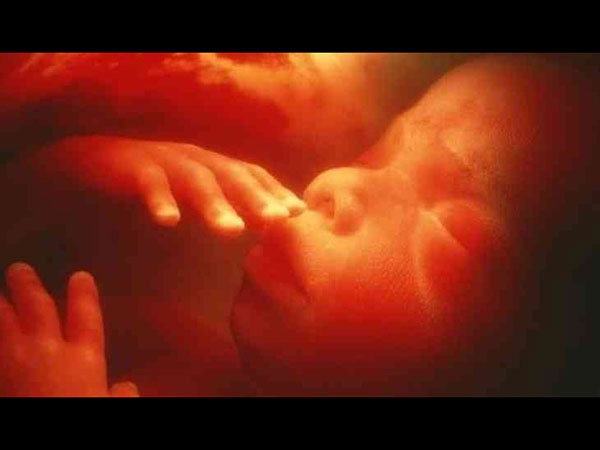

அறிவியலில் தினம் ஒரு அதிசயம் நடந்தபடி உள்ளது. இந்த நிலையில் பிறக்காத குழந்தைக்கு அறுவை சிகிச்சை நடந்ததை உங்களால் நம்ப முடியுமா? ஆம், தாயின் கருவில் இருந்து குழந்தையை வெளியில் எடுத்து அதற்கு அறுவை சிகிச்சை செய்யப்பட்டுள்ளது. இதனை நமது பாஷையில் சொல்லப் போனால் "இது ஒரு மெடிகல் மிராக்கில்" ஆகும்.

கருக்கலைப்பை பெற்றோர் ஏற்றுக் கொள்ளாத நிலையில், மருத்துவர்கள் கருப்பை அறுவை சிகிச்சை என்னும் புதிய சிகிச்சையைப் பற்றி கூறினர். இந்த வகை சிகிச்சையில் குழந்தை பிறப்பதற்கு முன்னரே, குழந்தையின் பிரச்னையை சரி செய்வது என்று கூறினார். அதாவது, குழந்தையை தாயின் கருப்பையில் இருந்து வெளியில் எடுத்து, அந்த குழந்தையின் முதுகுத்தண்டு பிரச்னையை சரி செய்து, மீண்டு தாயின் கருவில் வைப்பது தான் இந்த சிகிச்சை. இந்த சிகிச்சை மூலம் குழந்தை சாராசரி வாழ்க்கையை வாழ இயலும்.